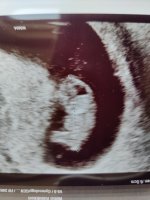

Nå er jeg 8+6 med nummer 2. Fikk se hjerte og sprelling i dag på TUL. Utrolig letter etter litt småblødninger og mye kramper![]()